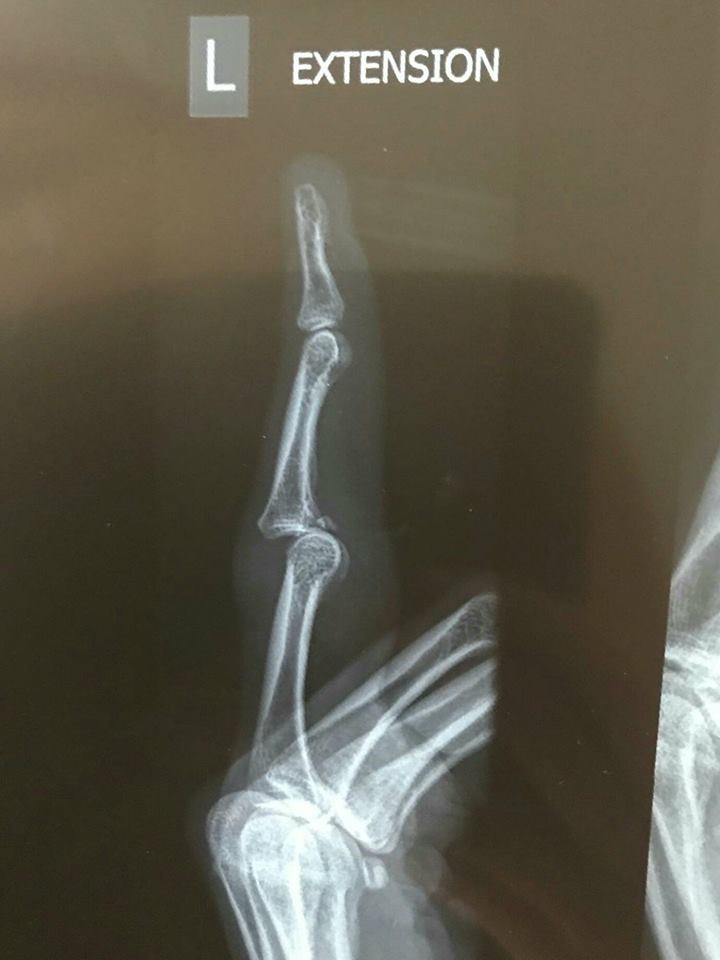

Lightning veteran Laura Hodges tomorrow goes in for surgery on her broken ring finger, an injury she suffered in the preseason - go here for more - but which she taped up and played with in Adelaide's first two games!

Check out the X-rays again. Whoa.

Yep. That's what you call a break.